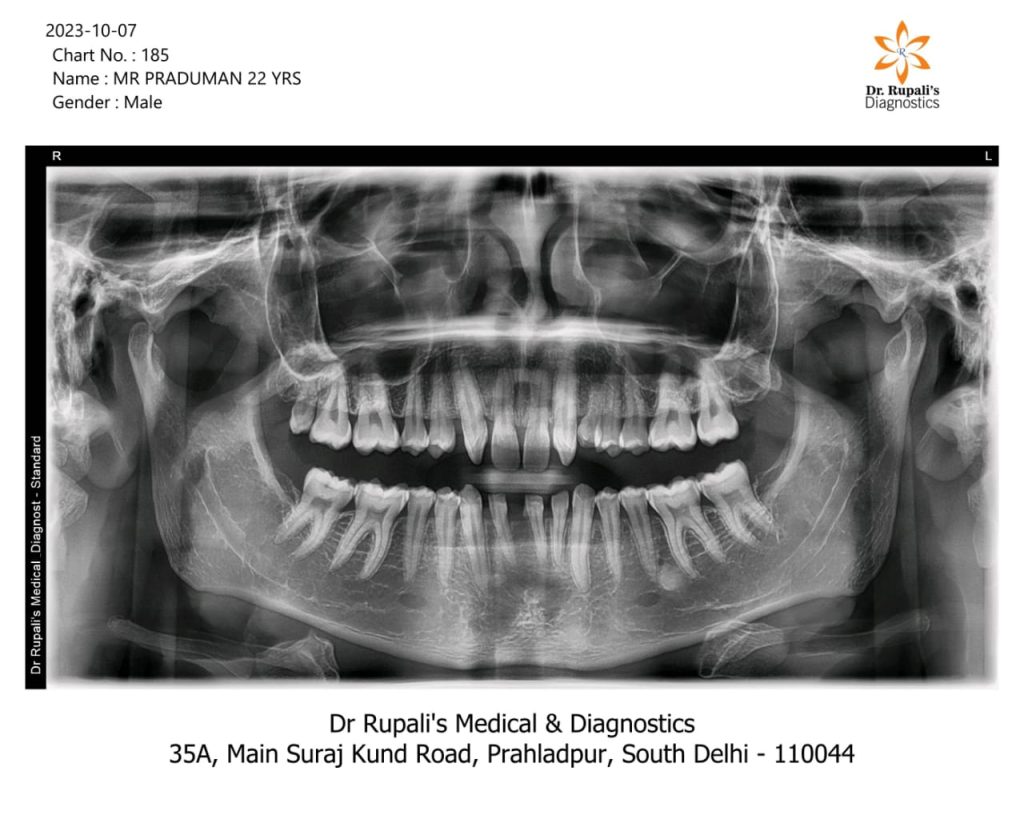

Dental X-Ray taken at Dr. Rupali’s Medical & Diagnostics

Our OPG Dental X-Ray Services (Digital X-Ray) offer a panoramic view of the entire oral and maxillofacial region, aiding in comprehensive dental diagnostics.

OPG X-rays are crucial for pre-surgical planning, providing detailed insights for dental procedures such as extractions, implants, and orthodontic treatments.

Assessing temporomandibular joint (TMJ) health is simplified with our OPG Dental X-Ray Services, helping in the diagnosis of TMJ disorders.

OPG X-rays contribute to precise orthodontic assessments, assisting in the planning and monitoring of orthodontic treatments.

Our services aid in the early detection of dental pathologies, supporting timely intervention and effective treatment planning.